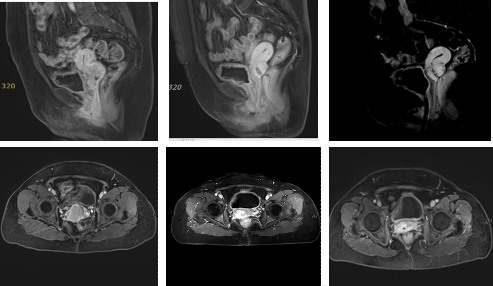

患者,女,74岁,盆腔核磁提示:宫颈占位性病变并异常强化,局部突向后穹隆,阴道上1/3受侵,病变大小3.8x3.1x4.4cm,病理提示:宫颈低分化鳞癌,右侧髂外淋巴结肿大约1.8 x 1.6cm,考虑转移,FIGO分期IIIC1r。HPV 16 (+)、SCC 50.2ng/ml.

注:图A、B为放疗前MR,3.8x3.1x4.4cm,SCC 50.2ng/ml;图C、D外照射治疗后、近距离治疗前病变2.2x2.0x1.8cm较前明显缩小,SCC 2.9ng/ml;图E、F为放疗后MR,放疗结束后:宫颈处信号欠均匀,强化减低,SCC 2.0ng/ml。